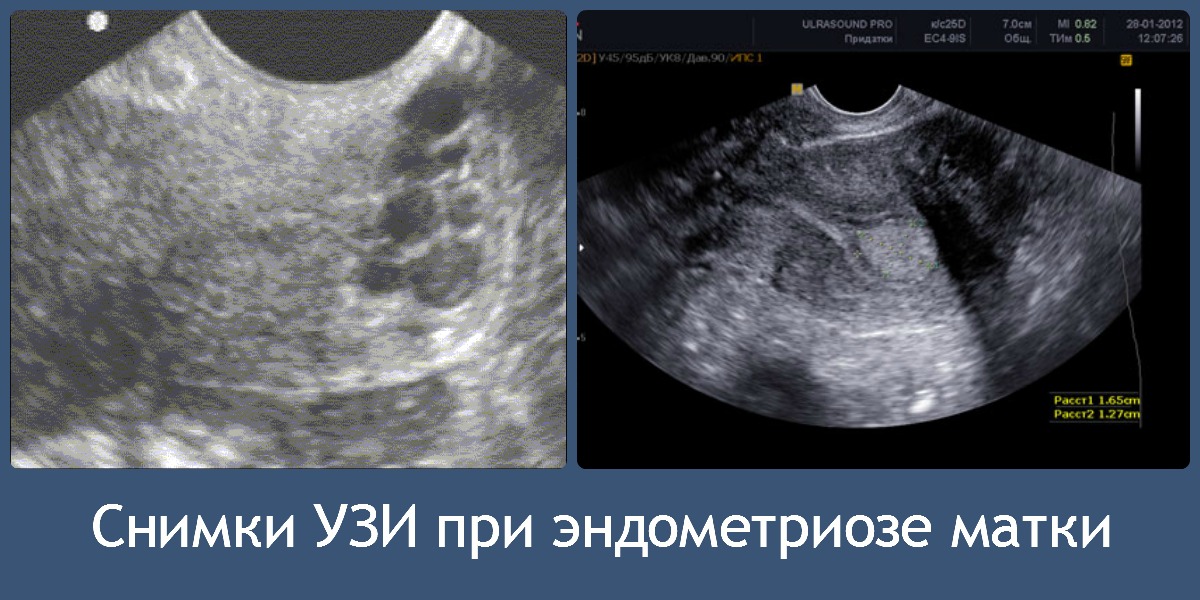

Ультразвуковое исследование

Данная методика позволяет охарактеризовать патологию по определенным критериям. Для эндометриоидных кист яичников характерно наличие плотной оболочки и гиперэхогенного содержимого.

При исследовании аденомиоза можно обнаружить участки с повышенной эхогенностью, а также неравномерные и зазубренные границы между эндометрием и миометрием. Также могут встречаться круглые включения диаметром около 5 мм. Узловые формы аденомиоза часто сопровождаются образованием полостей с жидкостью, достигающих диаметра примерно 30 мм.